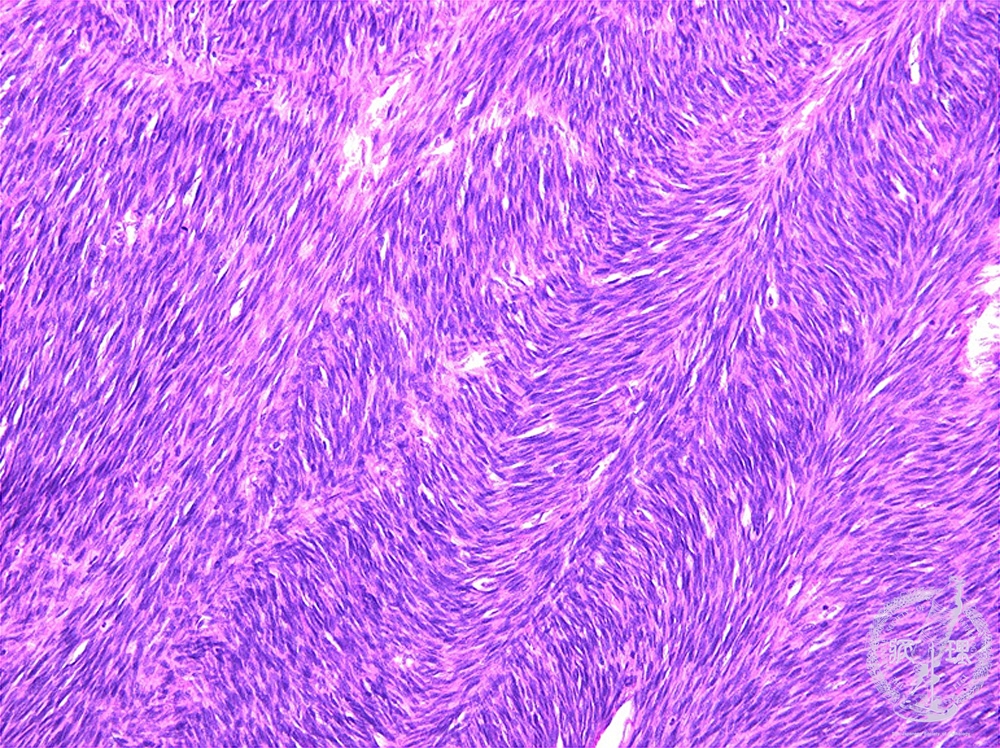

Microscopic findings (H.E. intermediate power view): Tumor cells with the characteristic structures, termed herring-bone pattern.